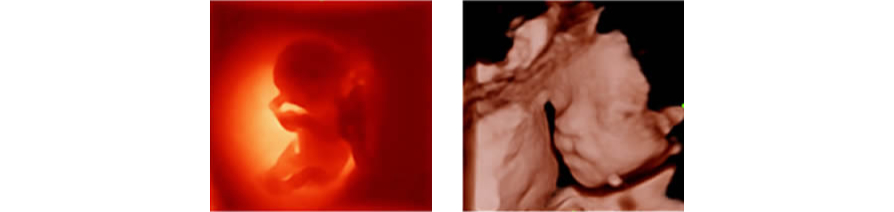

iLive

Ray-casting algoritmas?n? yeni sanal ???kland?rma modalitesi ile entegre eden iLive, insan derisine benzer g?rÞntÞlerle fetÞsÞn son derece ger?ek?i bir g?rÞnÞmÞnÞ olu?turur.